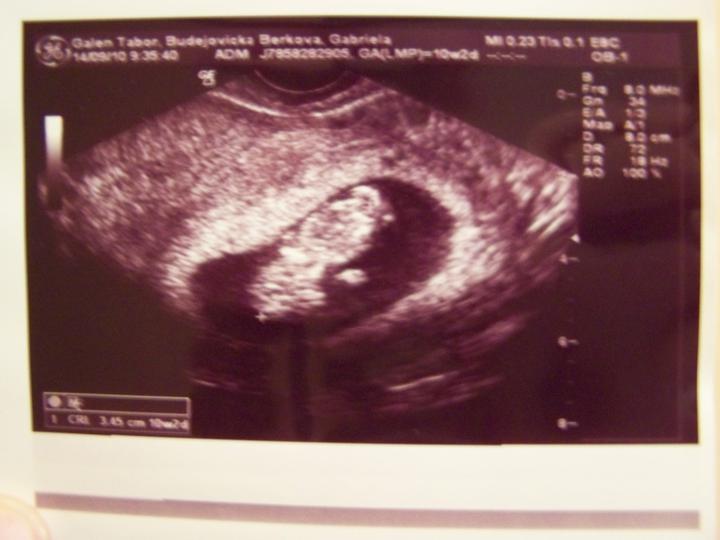

Screening dopadnul skvělě 🙂)) - negativní!!! Mimi se krásně vrtělo chichi